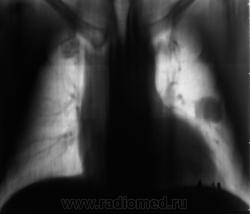

Начало 2008 года. При расшифровке флюорограмм, пациента "взяли на контроль", заподозрили периферический рак левого лёгкого (по "прямой" флюорограмме). Вроде-бы все правильно и логично?

В апреле 2009 года пациент пришел "для динамического наблюдения" - серия 2.

После повторного дообследования (апрель 2009 г) - 2 серия изображений, мы были твердо уверены, что пациент взят на учет..., но не тут-то было. В пятницу рентгенолаборант флюорографа попросил подойти и "глянуть снимок"...

Оказывается "данный" пациент направлен для прохождения профилактической флюорографии..., так как надо было поменять водительские права...?

Вот флюорограммы.

2. Конечно, мы на свой страх и риск, произвели дообследование, согласно стандарту. Итог дообследования представлен в серии 3.